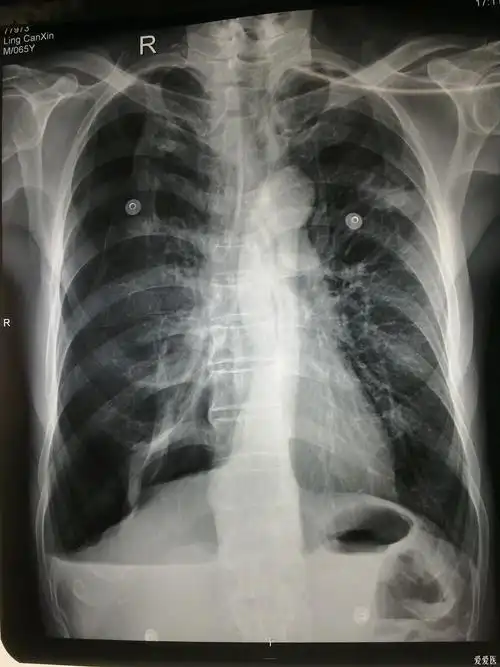

典型的结核病人液气胸胸片